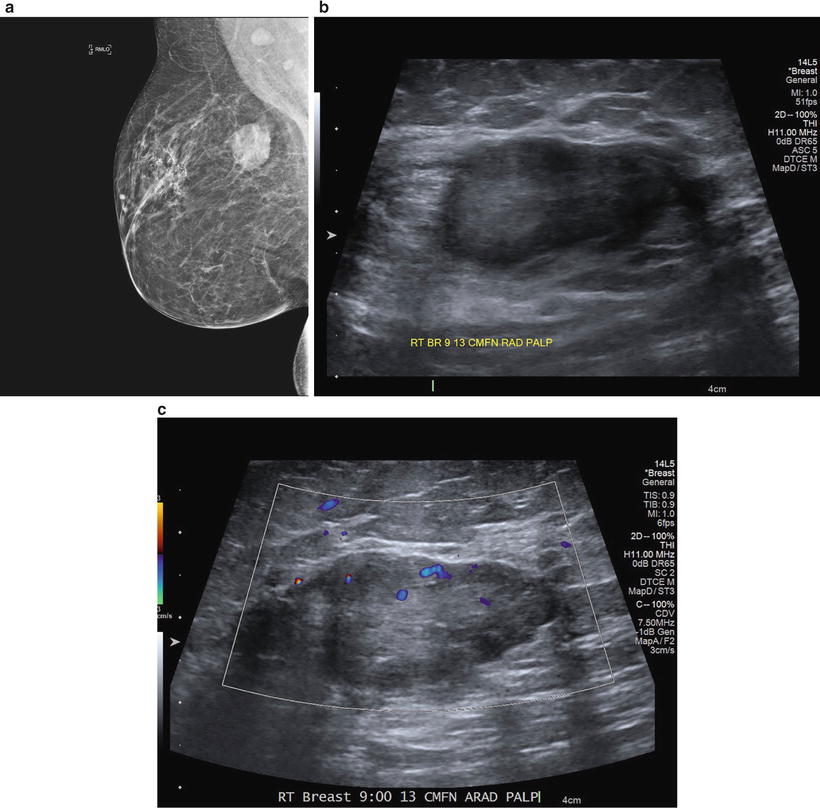

KRAS gene is the most common type of mutation reported in colorectal cancer (CRC) KRAS mutationmediated regulation of immunophenotype and immune pathways in CRC remains to be elucidated 535 CRC patients were used to compare the expression of immunerelated genes (IRGs) and the abundance of tumorinfiltrating immune cells (TIICs) in the tumor microenvironment between KRASmutant and KRAS. It is very frequent and can reach a considerable size Differentiation between lipoma and liposarcoma of low grade malignancy represents an important diagnostic problem, and valuable help in the differential diagnosis is provided by ultrasonography (US), computed tomography (CT), magnetic resonance imaging (MRI), biopsy and/or. For 30 years, Karen Minish has been sharing her gifts with the Bow Valley making us all the richer for it From sharing her incredible voice as a soloist with the Bow Valley Chorus, bringing Christmas joy through her carolling quartet, conducting the hospital choir in Banff, performing, or creating and directing the annual BVC Variety Show, creating incredible works of art, sharing her.

Ultrasound and MRI are the two major diagnostic imaging modalities for evaluating the soft tissues of the thigh Advances in ultrasound technology, including higherfrequency transducers, allow diagnosis of many types of musculoskeletal abnormalities, in many cases with an accuracy similar to that of MRI 1–4Ultrasound has additional advantages compared with MRI, such as lower cost and. Liposarcoma is a cancer that arises in fat cells in soft tissue, such as that inside the thigh or in the retroperitoneum It is a rare type of cancer that bears a resemblance to fat cells when examined under a microscope. Il liposarcoma è, tra le neoplasie della coscia, l’istotipo più comune (1240% nelle varie casistiche);.

It is very frequent and can reach a considerable size Differentiation between lipoma and liposarcoma of low grade malignancy represents an important diagnostic problem, and valuable help in the differential diagnosis is provided by ultrasonography (US), computed tomography (CT), magnetic resonance imaging (MRI), biopsy and/or. La localizzazione di partenza è quasi sempre profonda, a livello dei setti intermuscolari (in particolare per la coscia sono sedi preferenziali il m quadricipite e i m abduttori), o dai tessuti periarticolari, o dal grasso perirenale nei casi di liposarcoma retroperitoneale (5), Friedman e Egan (lO), Perry e Che (25), Edland (4), Mc Neer e. For 30 years, Karen Minish has been sharing her gifts with the Bow Valley making us all the richer for it From sharing her incredible voice as a soloist with the Bow Valley Chorus, bringing Christmas joy through her carolling quartet, conducting the hospital choir in Banff, performing, or creating and directing the annual BVC Variety Show, creating incredible works of art, sharing her.

Exosome isolation and tracking analysis EXOs were isolated from 24 h cell culture media by ultracentrifugation (UC) or ExoquickTC (EQ) (System Biosciences, Mountain View, CA, USA) methods according to standards procedures or manufacturer’s instruction, with minor modifications (Fig 1 a) For exosome purification, serum was depleted of bovine EXOs by ultracentrifugation at 100,000×g for 6. It is very frequent and can reach a considerable size Differentiation between lipoma and liposarcoma of low grade malignancy represents an important diagnostic problem, and valuable help in the differential diagnosis is provided by ultrasonography (US), computed tomography (CT), magnetic resonance imaging (MRI), biopsy and/or.